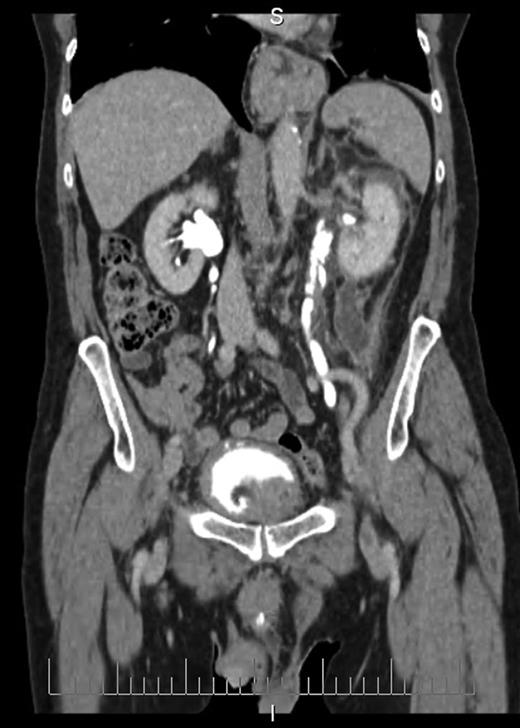

Blood tests revealed a Stage 3 acute kidney injury (baseline renal function was normal) with raised inflammatory markers and elevated PSA compared with baseline (Table 1). A mid-stream urine specimen sent for microscopy, cultures and sensitivities yielded no growth of organisms. A bedside bladder scan revealed a bladder volume of >999 ml, necessitating the insertion of a urethral catheter with a residual volume of 2.4 l, and intravenous antibiotics were commenced. An ultrasound scan (USS) of the urinary tract was performed to evaluate for the presence of hydronephrosis; but while this demonstrated a minor dilatation of the left renal pelvis, it also found a shallow fluid collection around the left kidney extending into the left lateral retroperitoneum, separate from the left psoas muscle (Fig. 1). In the urinary bladder, there was an irregular 4 cm mass on the left posterolateral aspect. In view of the findings, an urgent flexible cystoscopy was performed, revealing a massive median lobe of the prostate protruding up and back into the bladder; the ureteric orifices were not visualized because of this, and the bladder mucosa was normal. The patient subsequently underwent a computed tomography (CT) urogram, which showed bilateral fullness in the pelvicalyceal systems and confirmed a 4.8 × 4.4 × 2.8 cm fluid collection adjacent to the lower pole of the left kidney as detected on the USS, with perinephric stranding. The fluid collection was demonstrated to be extravasated urine on the delayed post-contrast images arising from a defect in the left proximal ureter, and extending down the left paracolic gutter (Figs 2 and 3). The massive prostate was also demonstrable (Fig. 3).

Coronal section CT image demonstrating fluid collection extending down left paracolic gutter. Also visible are massively enlarged prostate and urinary extravasation from left ureter.